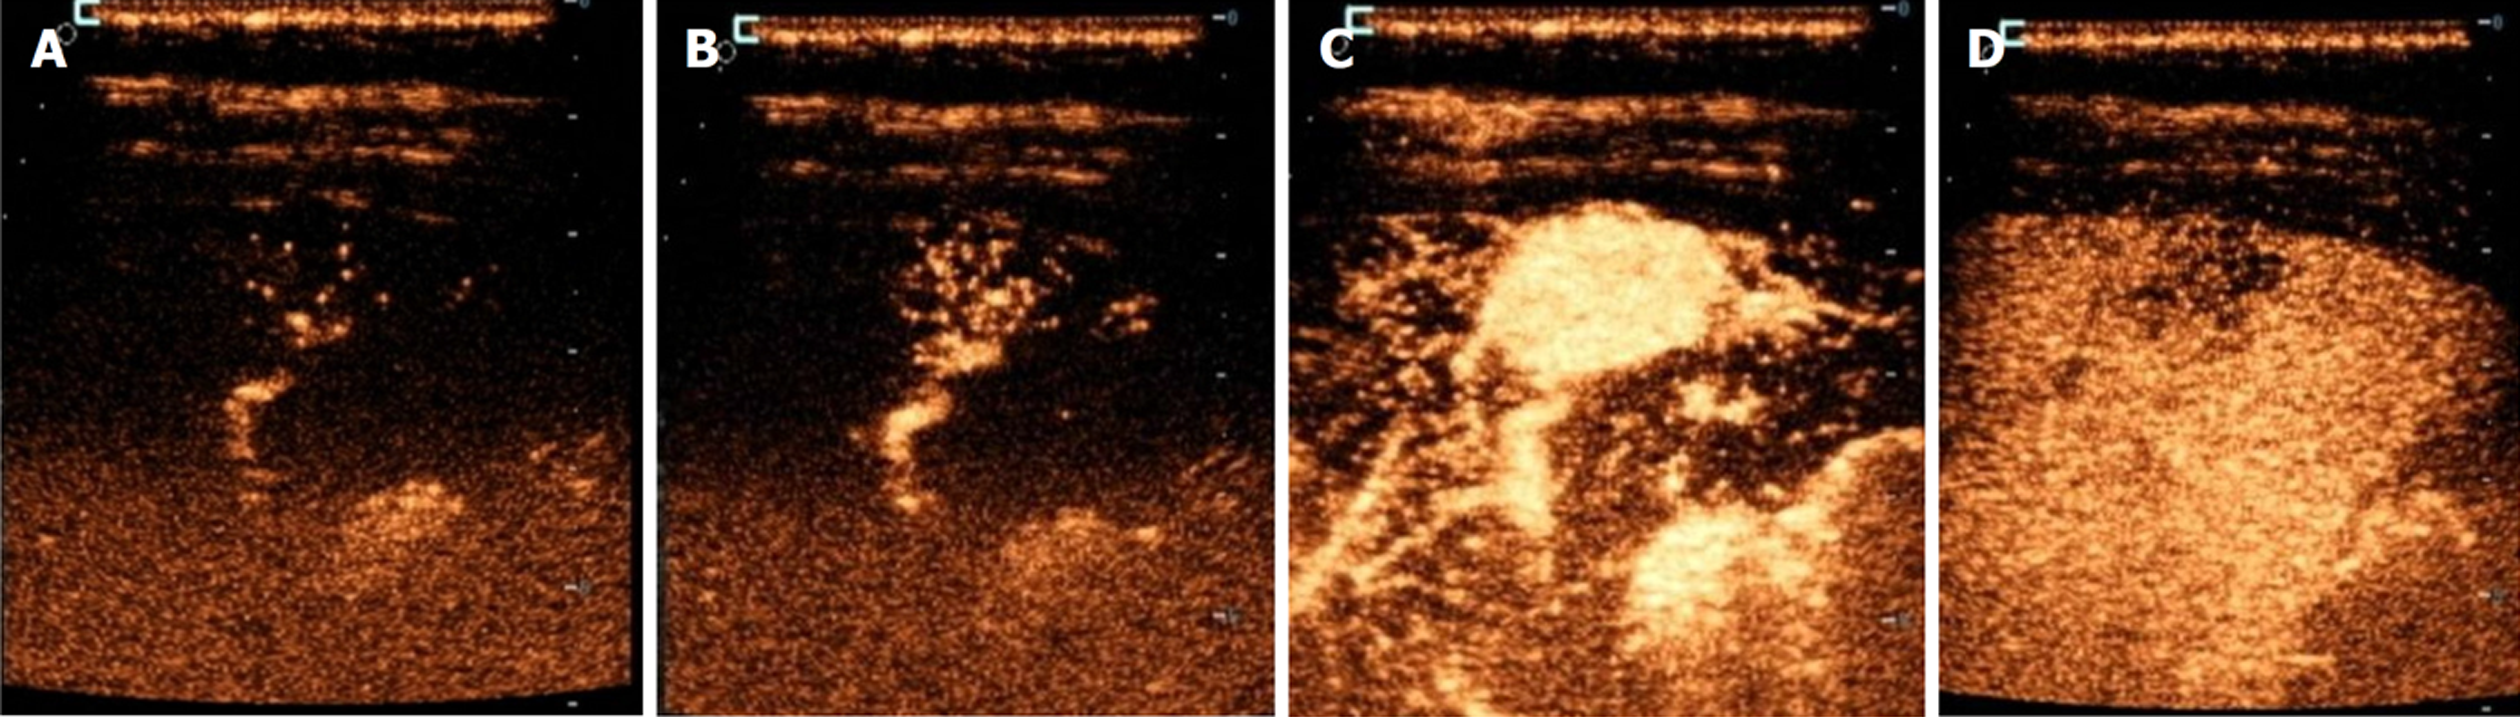

FNH大小<3 cm患者均表现为动脉期早于肝实质的快速高增强, 增强方式以泉涌状增强为主, 未见分枝状增强, 相对肝实质增强-消退变化均表现为快进慢出; >5 cm患者大多表现为迟于肝实质的增强, 以分枝状增强为主, 未见泉涌状增强, 且>5 cm患者中央瘢痕检出率较高, 相对肝实质增强-消退变化大多表现为慢进慢出. 整体比较显示, 不同FNH大小患者相对肝实质增强时间、动脉期的增强方式、中央瘢痕检出率、相对肝实质增强-消退变化比较, 差异有统计学意义(P<0.05); 进一步的卡方分割法比较显示, <3 cm患者早于肝实质增强、泉涌状、快进慢出占比显著高于3-5 cm、>5 cm患者(P<0.0167), 且3-5 cm患者高于>5 cm患者(P<0.0167); >5 cm患者迟于肝实质、分枝状增强、中央瘢痕、慢进慢出占比显著高于<3 cm、3-5 cm患者(P<0.0167), 且3-5 cm患者显著高于<3 cm患者(P<0.0167). 整体比较显示, 不同FNH大小患者滋养动脉检出情况比较差异无统计学意义(P>0.05). 见表1和表2. 不同FNH大小患者CEUS表现见图1.

本研究结果发现, <3 cm的患者表现出典型的早于肝实质的快速高增强(100.00%)和泉涌状增强模式(占该组71.43%), 这一现象与小型FNH特有的血管构筑密切相关. 小型FNH病灶内新生血管密度更高, 血管直径更均匀, 且异常动脉-门脉分流率高, 这解释了其快速均匀增强的特征[16,17]. 本研究中<3 cm FNH均表现为快进慢出模式, 这与既往研究[18]相似. 随着FNH增大, 本研究观察到增强时间延迟(3-5 cm组21.21%迟于肝实质, >5 cm组94.12%迟于肝实质)和分枝状增强占优(3-5 cm组30.30%, >5 cm组52.94%)的特征转变. 这种改变源于大FNH内部的结构异质性: (1)中央纤维瘢痕区域血管密度降低, 且常伴玻璃样变; (2)异常血管迂曲度指数随着FNH增大, 逐渐升高; (3)门脉供血比例显著提升, 这些病理改变导致造影剂在病灶内的分布不均和廓清延迟, 形成特征性的慢进慢出模式(占>5 cm组的94.12%)[19]. 本研究发现>5 cm FNH的中央瘢痕检出率达58.82%, 远高于<3 cm、3-5 cm患者, 这与瘢痕面积与FNH体积的正相关性特征相符[20].